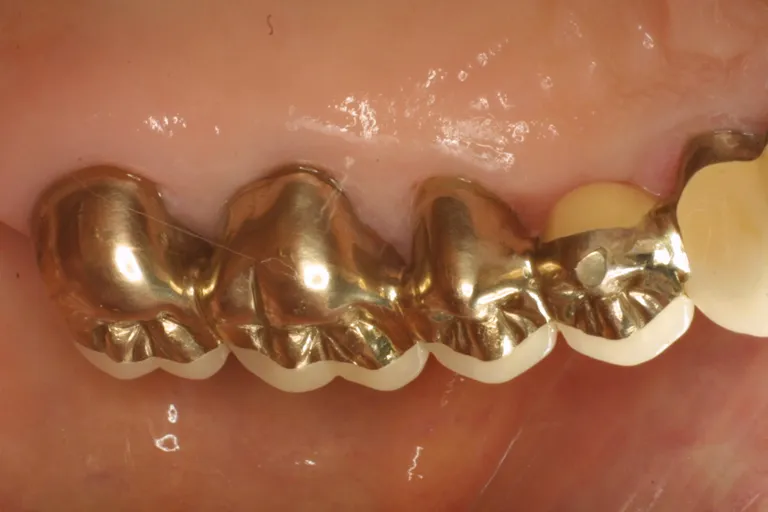

■自費対応の被せ物

通常は、金の含有量の多い白金加金を用います。この金属は、良好な物性を持ち、型どりした歯に上手く合わせることができます。

保険対応の治療が、目で見た範囲での技工である一方で、自費対応の治療では、技工士が20倍の実態顕微鏡で作業し、型どりした模型上で、縁の合わせ方が20ミクロン(50分の1ミリ)を目標にします。

この精度で被せ物を製作すると、セメントで付けたあと、50ミクロン程度の適合度になります。このレベルの精度があれば、縁からバイ菌が侵入しにくくなることがわかっています